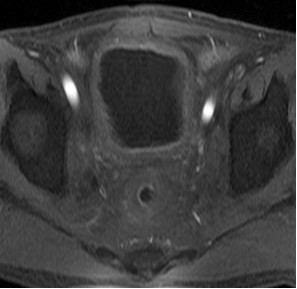

患者男性,63岁。诊断:直肠癌术后Ⅳ期,膀胱、盆腹腔及骨多发转移。患者2013年3月确诊后,行放化疗,后吃中药治疗,2015年12月病情恶化。2016年1月,盆腔MRI检查提示直肠癌侵及膀胱及周围组织,伴骶前转移及骶骨转移。2016年3月,CT检查提示直肠占位病变伴膀胱、前列腺、部分骶椎输尿管受侵,右侧大网膜强化结节,转移不除外,肠系膜及腹膜后淋巴结增大。肠镜检查提示肛管见菜花样肿物,肛管狭窄。化疗一疗程后,患者不能耐受而终止。为寻求下一步治疗方案,患者找到全球肿瘤医生网A45专家,经过中美癌症专家综合会诊,制定A45治疗方案。

患者于2016年6月开始A45治疗,一个疗程后复查,膀胱及直肠病灶明显缩小,肛周复发灶较前缩小,血尿症状消失,疼痛症状消失,其他症状显著缓解。